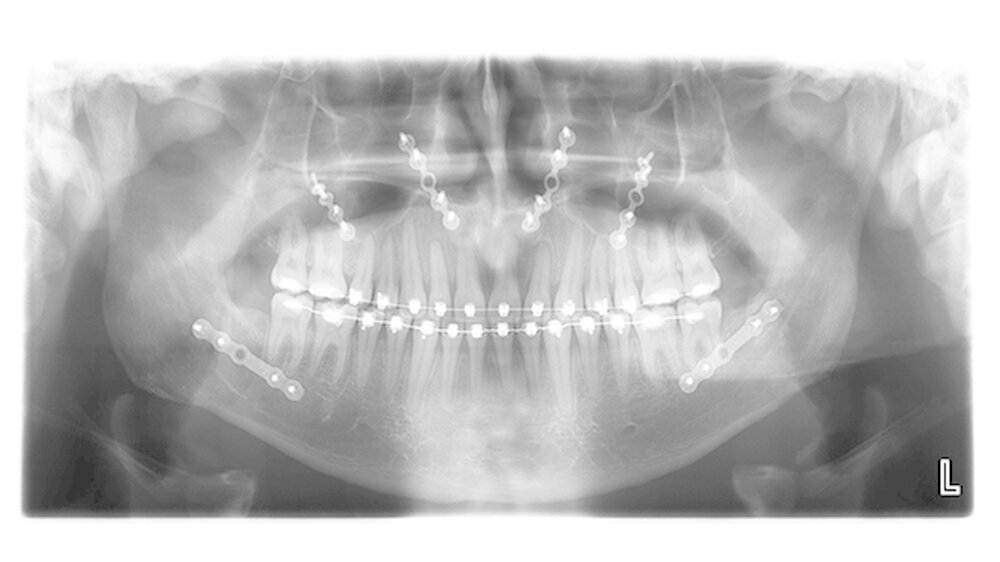

Die Abbildungen 1 und 2 zeigen die klinische Situation bei Erstvorstellung: Der Unterkiefer ist zu prominent. Der Oberkiefer und das Mittelgesicht liegen zurück. In der Front liegt ein umgekehrter Überbiss vor. Der Unterkiefer steht vor dem Oberkiefer. Das erschwert das Abbeißen und Kauen der Nahrung. Die Scans (siehe Abbildungen) dokumentieren, wie aufwendig die virtuelle Operationsplanung erfolgen musste.

Nun muss die Biss-Situation anhand des Computer gefertigten Biss-Schlüssels exakt eingestellt werden, bevor mit zwei Millimeter dicken Osteosyntheseplatten aus Titan der Knochen in der neuen Position mit Hilfe von Titanschrauben fixiert wird. Im Unterkiefer erfolgt die Schnittführung im Zahnfleisch hinter dem letzten Backenzahn beidseits. Nun wird der Unterkiefer mit spezieller Technik durchtrennt. Dies erlaubt eine Verschiebung der Zahn tragenden Basis vom Gelenk tragenden Knochenabschnitt des Unterkiefers.

Bei der Präparation wird der im Unterkieferknochen verlaufende Nervus alveolaris sorgfältig geschont. Die neue Position wird mit einem zweiten Biss-Schlüssel, der die endgültige Biss-Situation einstellt, zugeordnet und mit Osteosyntheseplatten und -schrauben gesichert.

Die Platten und Schrauben fixieren den Knochen in der Art und Weise, dass der Patient postoperativ weiche Kost essen darf. Nach einer Woche werden die Fäden entfernt, die kieferorthopädische Feineinstellungdes Bisses kann jetzt beginnen.